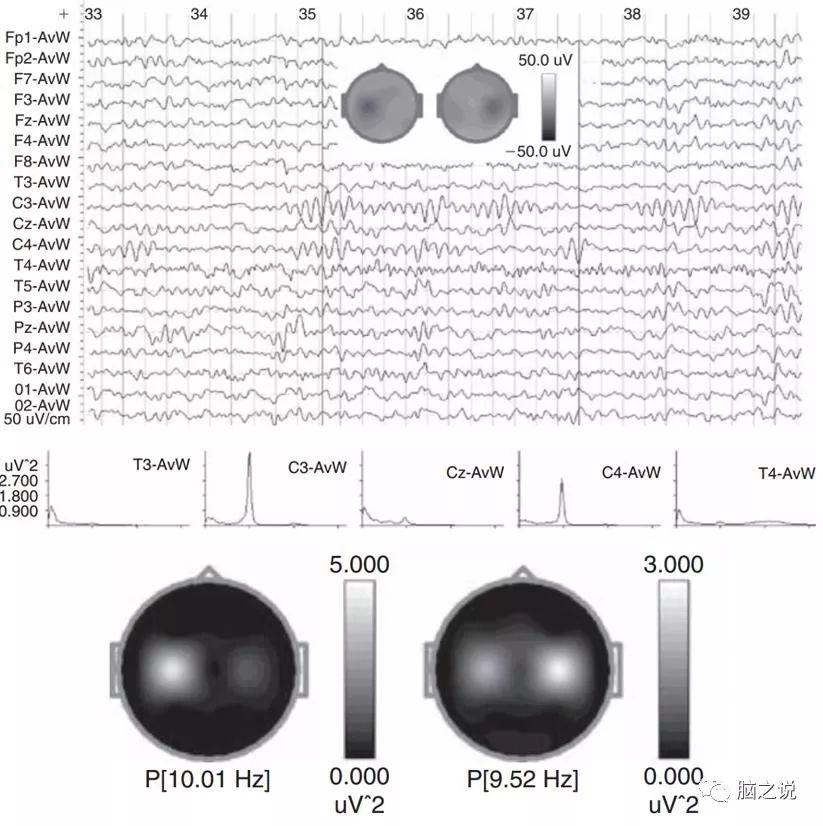

如图1所示,被试睁眼静息态下我们可以在C3和C4电极上观察到相互独立的alpha节律,这些alpha节律具有尖锐的负波,使人很容易想起希腊字母μ (mu),因此这些alpha节律又称为mu 节律。此外,mu节律又称为感觉运动 alpha节律,主要是由于其主要位于sensory-motor皮层区域。Mu节律可以被手运动、手的运动想象等所阻断,反之,肌肉的放松可以增强mu节律。

图1